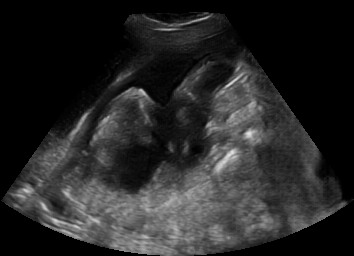

Real in-vivo images. 22 ultrasound sequences were collected using a GE Voluson E8 machine during standard fetal screening exams of 8 patients. Each sequence is several seconds long. We extracted all 4427 frames and resize them to , see Fig. 2 for some examples. The resulting image set was randomly split into training-validation-test sets by a 80-10-10% ratio.